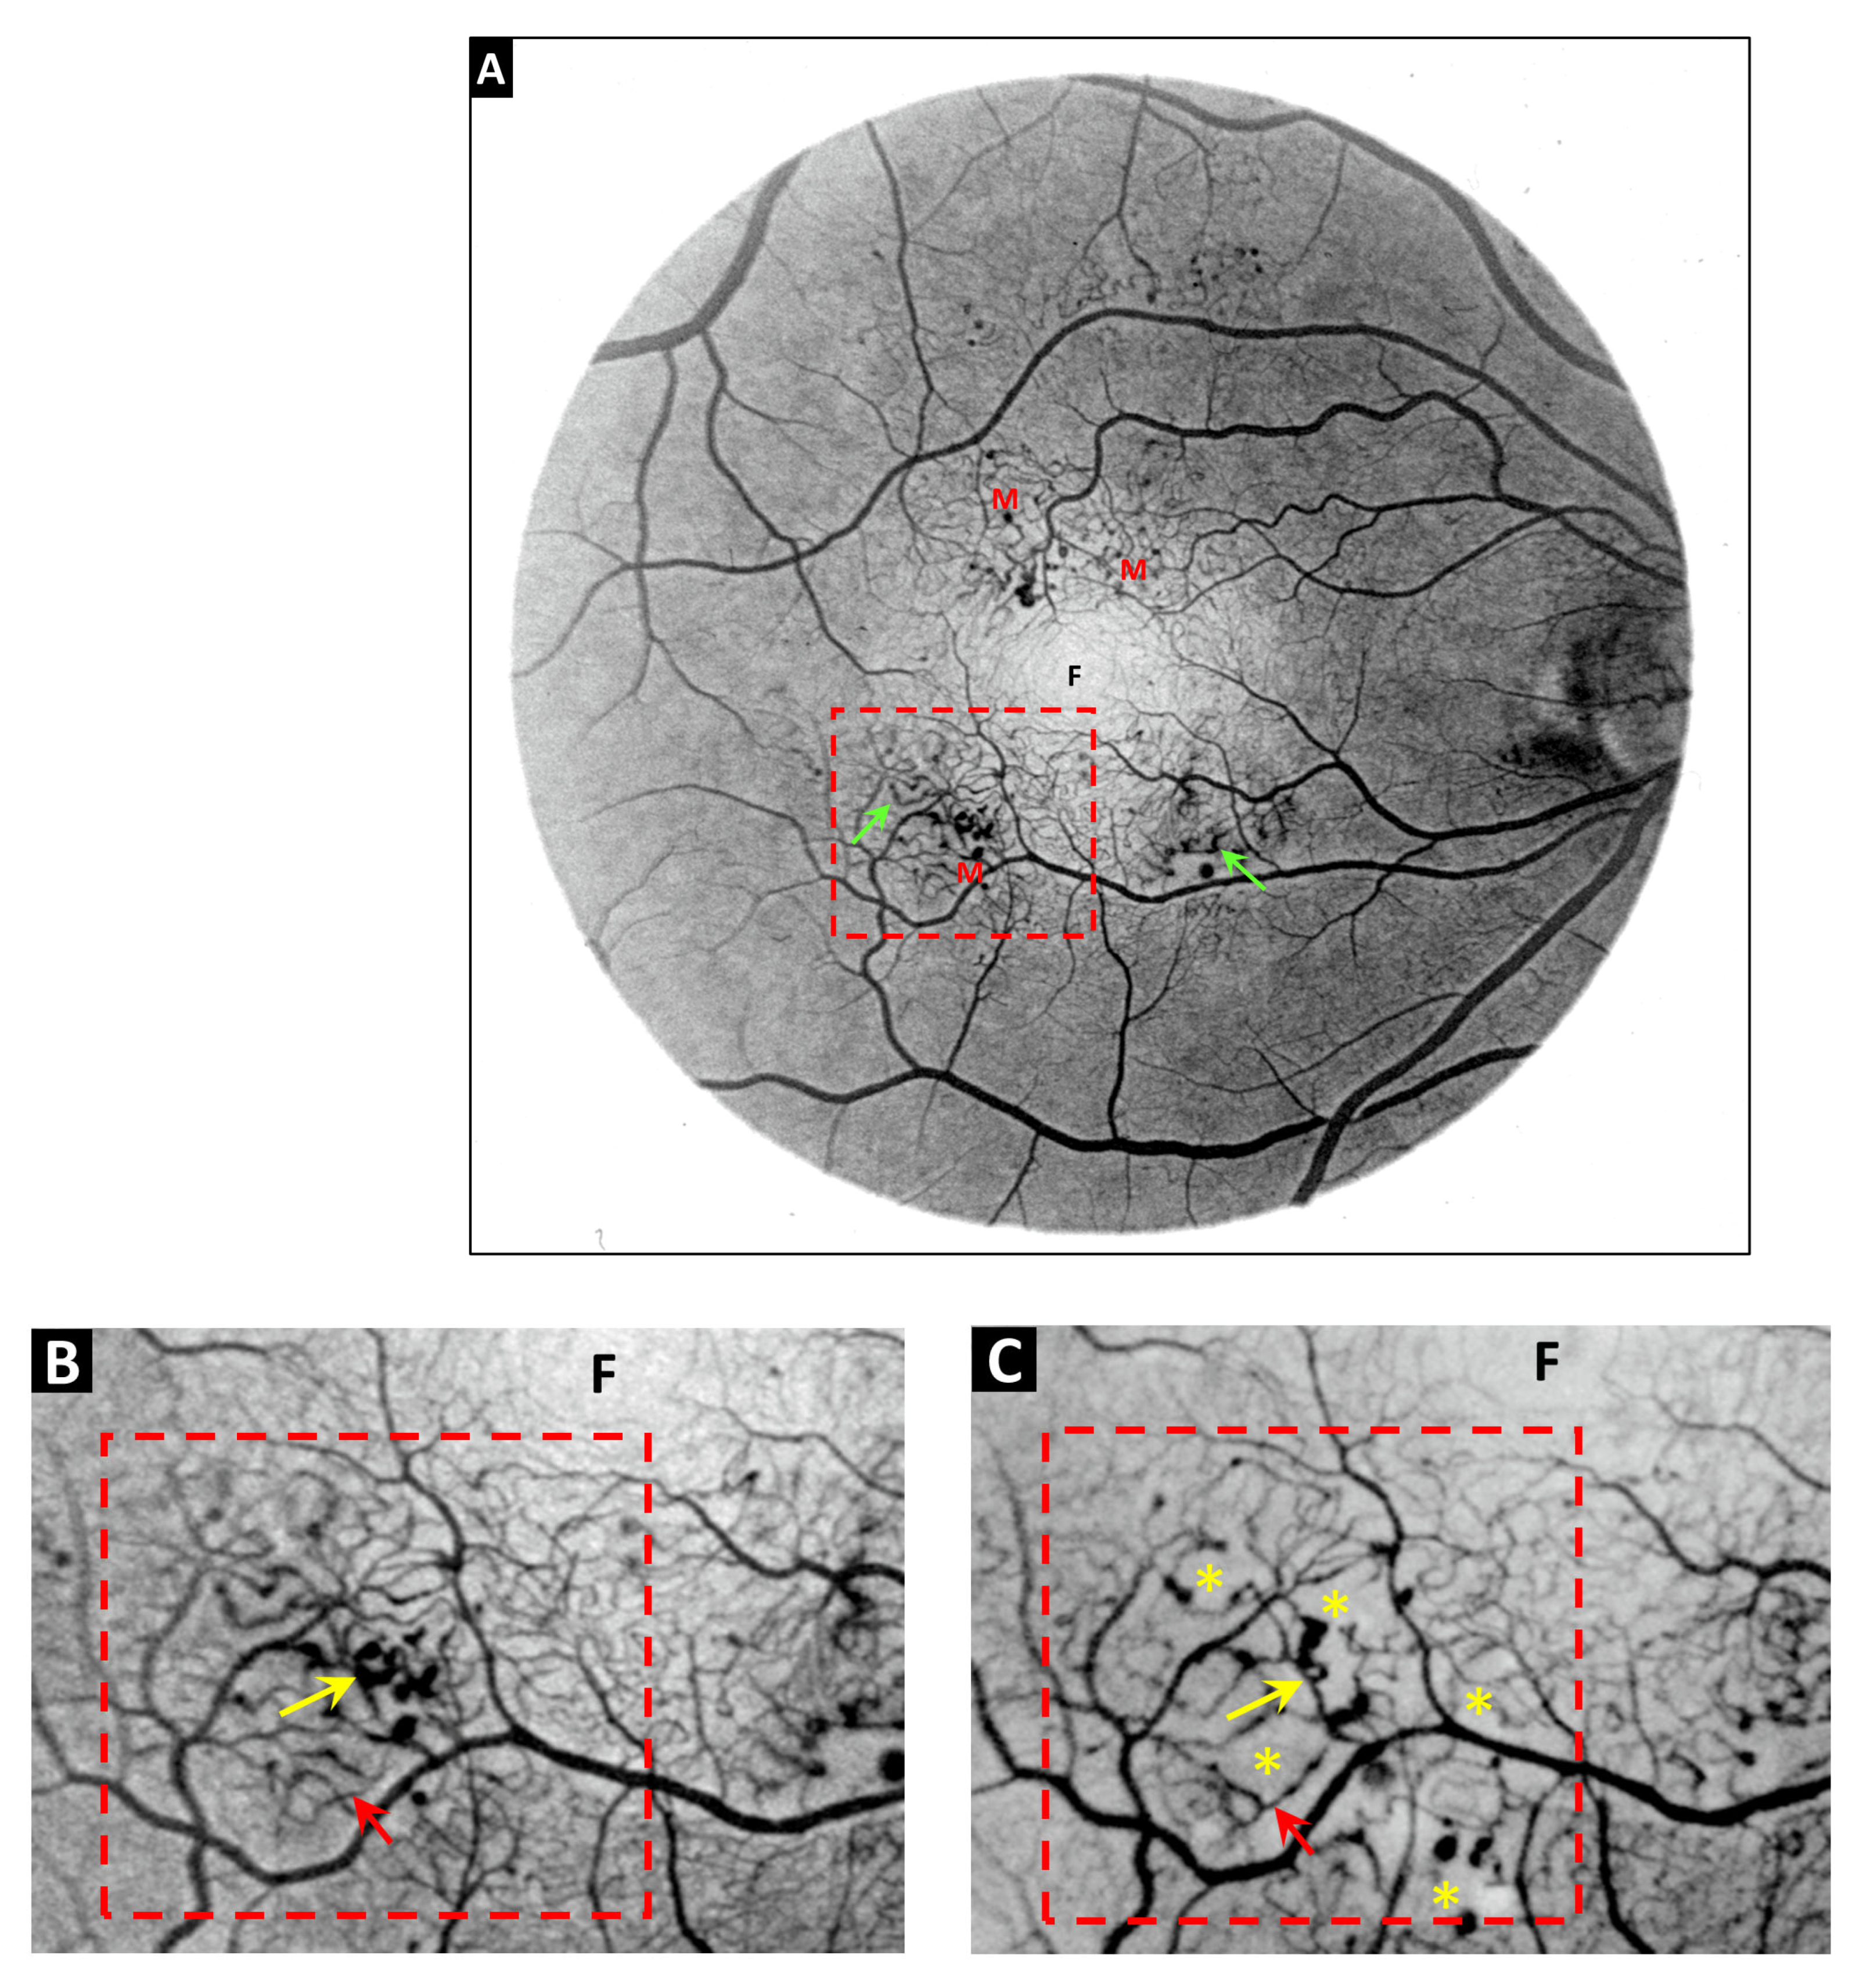

- Amoaku, W.M.K.; Archer, D.B. Fluorescein angiographic features, natural course and treatment of radiation retinopathy. Eye 1990, 4, 657–667. [Google Scholar] [CrossRef]